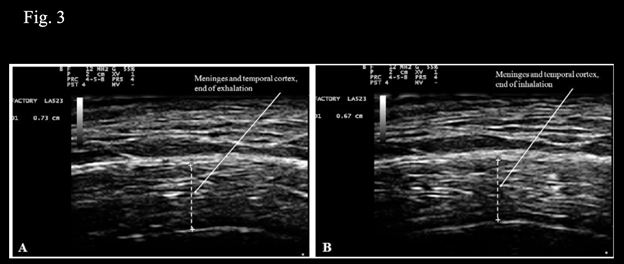

Step 3 of the procedure described in Klinghardt and Ruggiero10 consists of application of therapeutic ultrasounds. In case of Neuro-COVID-19, this step has a double function. 1. Force the exit of SARS-CoV-2 from reservoirs or sanctuaries in brain tissue. 2. Neutralize the virus thanks to the disrupting effects of ultrasounds on viral structures with particular reference to spike proteins.11 Here, it is reported how tailoring the procedure described in Klinghardt and Ruggiero10 to Neuro-COVID-19 requires an additional step that consists in taking into account the movements of contraction and expansion of the brain that occur synchronously with breathing. Previous observations14 of brain movements using transcranial ultrasonography evidenced the known pulsatile movements synchronous with the cardiac cycle as they were reported in studies using MRI.21 In addition to the movements associated with the cardiac cycle, rhythmic movements of contraction and expansion associated with the respiratory cycle were observed. Fig. 3, shows the total thickness of the meninges and the cortex of the temporal lobe at the end of forced voluntary exhalation (Figure 3A, thickness 7.3 mm), or at the end of forced voluntary inhalation (Figure 3B, thickness 6.7 mm). These observations are consistent with the results reported by Turner et al.22 who, using f-MRI, described similar rhythmic pulsations of the brain associated with the respiratory cycle. These movements of contraction and expansion of the brain are of significant magnitude and are to be considered the respiratory equivalent of the Monro-Kellie doctrine that concerns the cardiac cycle and is responsible for cerebrospinal fluid (CSF) flow.23 However, at variance with the movements associated with the cardiac cycle, the movements of the brain associated with the respiratory cycle can be controlled voluntarily as demonstrated in Fig. 3. Therefore, in the context of exploiting the effects of ultrasounds in Neuro-COVID-19, it is proposed to apply the therapeutic ultrasounds every other voluntary exhalation when the thickness of the meninges and cortex is maximal and the movement of expansion of the brain has reached its apex. The rationale for such a timed approach consists in the evident greater hypoechogenicity of the brain structures at the end of forced voluntary exhalation (Figure 3A); such an ultrasonography finding corresponds to a greater amount of extracellular liquid that in turn translates in reduced ultrasound velocity, thus maximizing the mechanical disruptive effects of the ultrasound waves.24 The rationale for applying bursts of therapeutic ultrasounds alternatively, at end of every other exhalation, consists in the observation that expansion of the brain corresponds to increased removal of CSF.21 The burst of therapeutic ultrasounds is aimed at forcing the exit of SARS-CoV-2 from reservoirs or sanctuaries at the same time mechanically disrupting its molecular structures; during the following respiratory cycle, the virus and its debris would be removed by the flow of CSF and then the cycle could be repeated. In addition, it has to be considered that transcranial ultrasounds show anti-inflammatory and anti-edema effects,25 and ultrasounds may favor CSF drainage in analogy with their known effects on lymphatic drainage.26

Figure 3 Measurement of combined thickness of the meninges and the cortex of the temporal lobe at the end of forced voluntary exhalation (A), and inhalation (B).